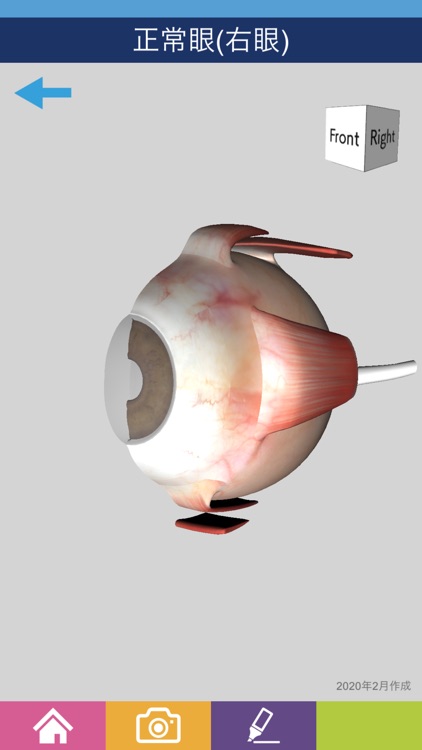

【公式】フジのお歳暮・冬ギフト 楽天市場】 目玉 眼球 眼 眼球 目 6倍拡大模型 眼球モデル 人体 人体模型の詳細情報

楽天市場】 目玉 眼球 眼 眼球 目 6倍拡大模型 眼球モデル 人体。CLA眼球模型|株式会社テイエムアイ。51aaFPgbKXL._AC_UF894,。【新鮮で良質】農薬不使用 化学肥料不使用 生ぬか ぬか床 米ぬか。IFNEが主催する国際ハンズオン・ワークショップにて精密医療模型。楽天市場】【大阪人体模型センター 正規品】【送料無料】 人体。人体模型 眼球/5倍大,眼瞼と涙器付。楽天市場】【大阪人体模型センター 正規品】【送料無料】 人体。Amazon.co.jp: ヒト眼球10部構成モデル眼球感覚器官モデル及び。imgrc0086707452.jpg。61Sxs9iafOL._AC_UF894,。即配】(KT) 72mm ZX II (ゼクロスII) プロテクター ケンコー。楽天市場】【大阪人体模型センター 正規品】【送料無料】 人体。紐を引くと瞼が閉じたり開いたり左右に動いたりします。